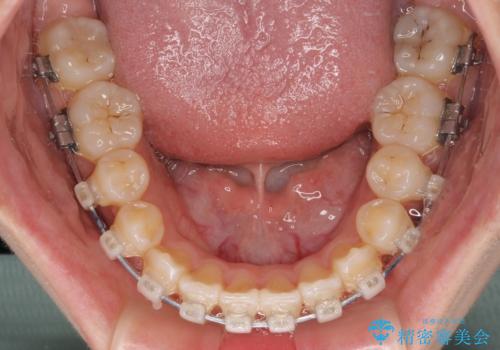

- クリアブラケット

上顎歯列が狭窄していたため、急速拡大装置により上顎骨を側方に拡大し、その後ワイヤー装置にて矯正治療を行うこととしました。

急速拡大装置で上顎骨を十分に拡大できたことで、非抜歯で八重歯を歯列に納めることができました。